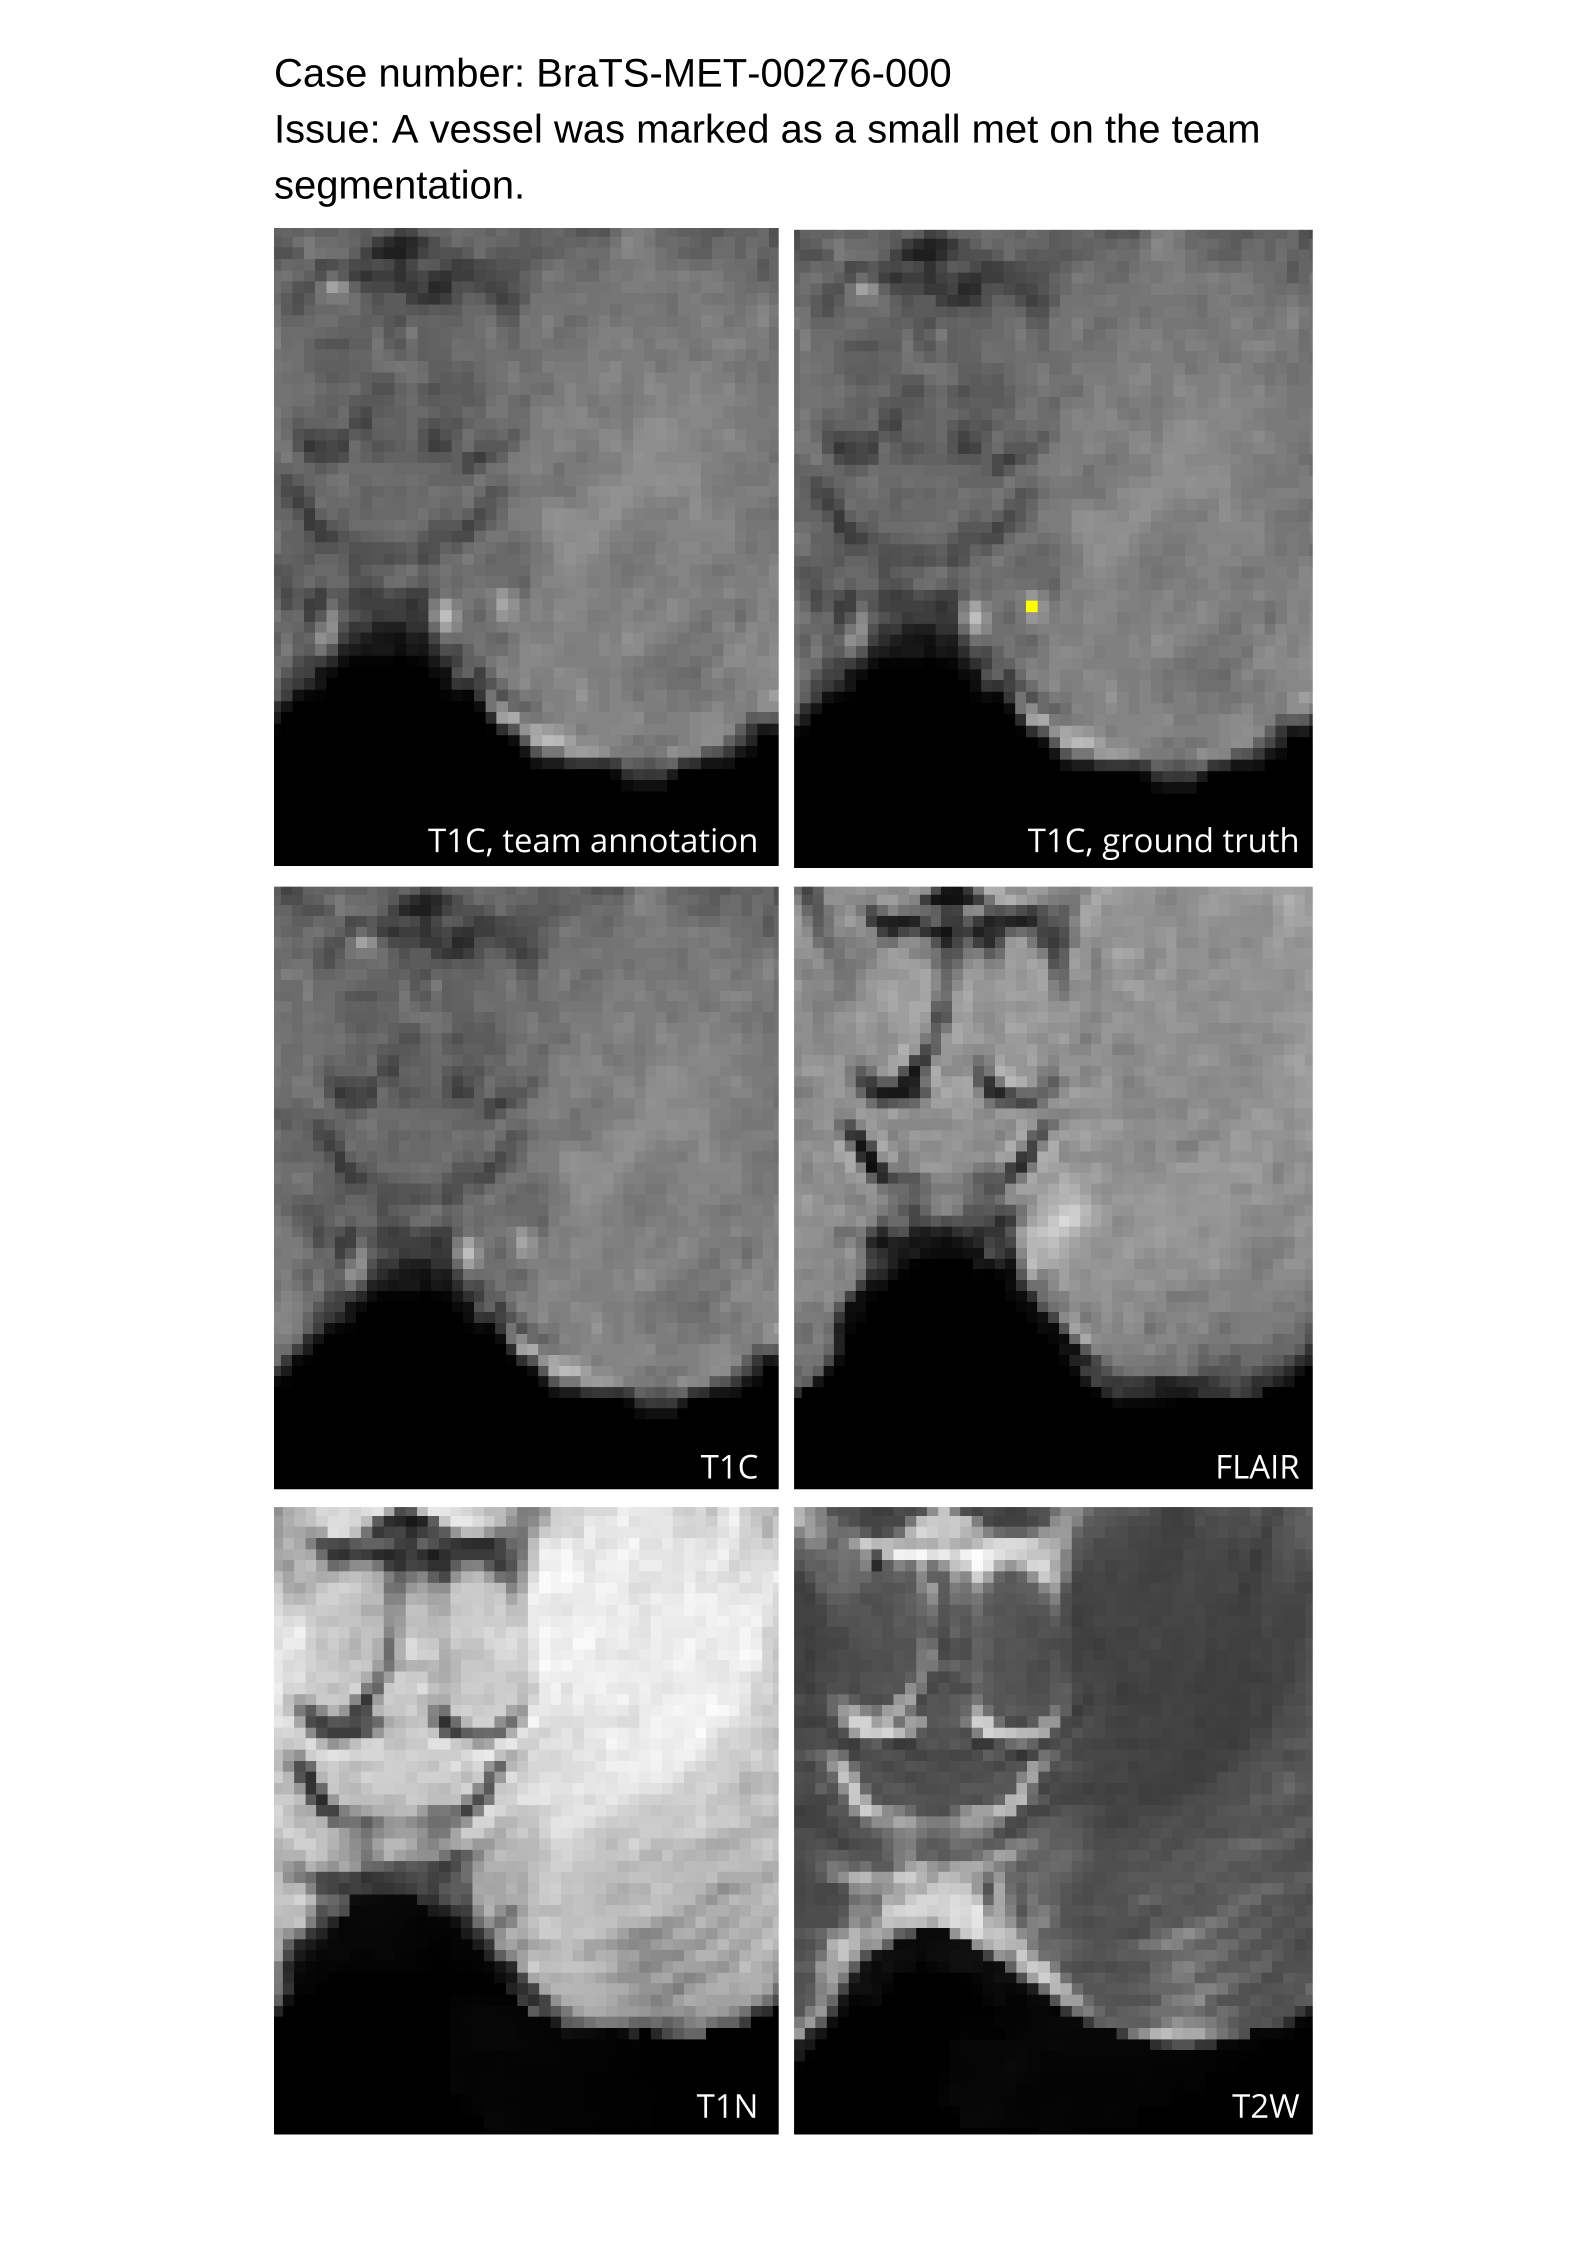

4.9 Common Errors of Automated Segmentations

Based on observations from previous BraTS challenges, common errors in automated segmentations were identified. The most typical errors in the current challenge included:

The segmentation of non-enhancing lesions that have intrinsic T1 hyperintensity. Voxels with intrinsic T1 hyperintensity were manually removed from ET segmentations.

These insights led to specific adjustments in the annotation process to enhance accuracy.